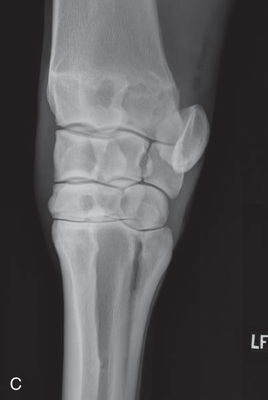

| Carpus | Dorsoproximal-palmarodistal (DPr-PaDi) | Dorsopalmar (DP) |

| Lateromedial extended (LM) | Lateral (L) | |

| Lateromedial flexed (LM) | Flexed lateral (L) | |

| Dorsoproximal 45-degree lateral–palmarodistomedial oblique (DPr45L-PaDiMO) | DLPMO | |

| Dorsoproximal 45-degree medial–palmarodistolateral oblique (DPr45M-PaDiLO) | DMPLO | |

| Optional views | Dorsoproximal-dorsodistal oblique flexed (DPr-DDiO) | Skyline |

The carpus consists of three principal joints with articulation between adjacent bones in each row of carpal bones. This causes overlying images, which may confuse interpretation. Consequently, it is recommended to obtain a minimum of five standard views.3

Oblique views of the carpus are as follows: